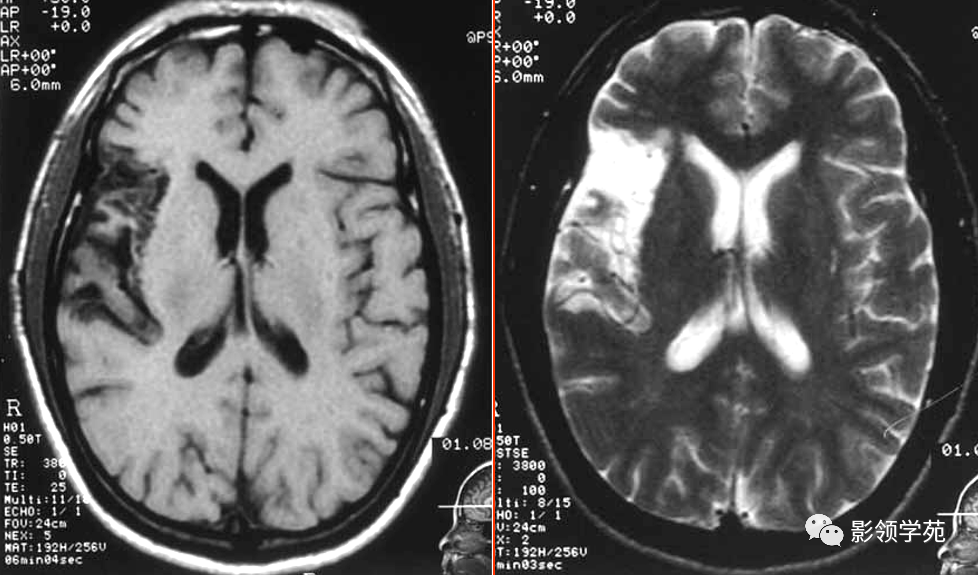

MRI表现

超急性期(0~6 h) 发病2 h,T2WI可呈高信号,部分病例30 min便可显示。

急性期(6~72 h) 梗死区水肿发展,T1,T2值进一步延长。

亚急性期(3~10 d) 3 d后水肿最重,占位明显,梗死范围仍增大,脑回状强化明显。以上三期DWI均为高信号

慢性早期(11~30 d) 坏死组织被清除,水肿渐消退,梗死区周围出现新生血管。仍呈脑回状强化,可出现坏死囊变,易出现梗死后出血。

慢性晚期(>30 d)梗死范围小、治疗及时,仅有局部脑萎缩。梗死区明显的胶质增生,引起脑萎缩、囊性脑软化灶。